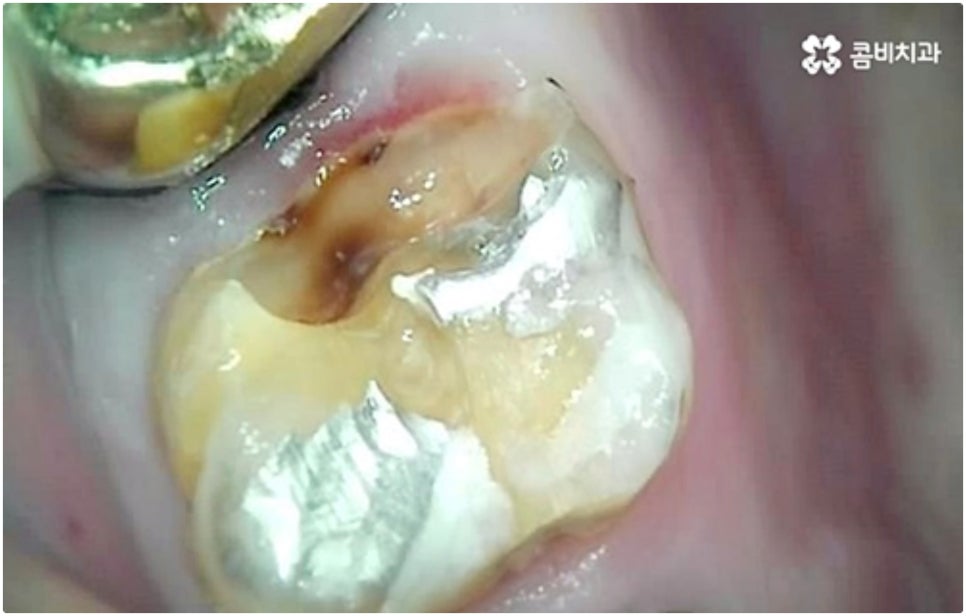

모든 치아가 위치와 모양이 제각각 다른데 특히 어금니는 구강 내 깊은 곳에 있고 주름진 저작면을 가지고 있기 때문에 관리할 때 더욱 주의할 필요가 있습니다. 꼼꼼하게 칫솔질을 해준다고 해도 음식물 찌꺼기가 남게 될 가능성이 높아 충치나 치주염 등 구강 질환이 빈번하게 발생할 수 있기 때문인데요, 이때 빠른 발견으로 초기 대처를 해주지 못하면 내부 신경까지 손상이 깊어져 치아를 발치하고 어금니임플란트 시술을 받아야 할 상황까지 발생할 수 있어요.

구강 질환 때문이 아니더라도 저작 기능의 핵심적인 역할을 담당하고 있어서 외부 충격 (실수로 딱딱한 것을 씹는 일 등) 에 노출될 위험도 큰데요, 만약 부러지고 금이 갈 때 뿌리까지 갈라졌다면 해당 어금니는 살릴 수 없고 인공 치아로 대체해야 할 거예요.

어금니는 저작력이 많이 걸리는 치아이기 때문에 보철물 제작에 있어서도 강한 자극에 잘 견딜 수 있는 튼튼한 재질을 고르는 것이 중요한데 요즘은 이러한 내구성과 함께 심미적인 부분도 함께 고려하는 추세라서 어금니임플란트 시술시 지르코니아 크라운을 선택하시는 분들이 많이 있습니다.